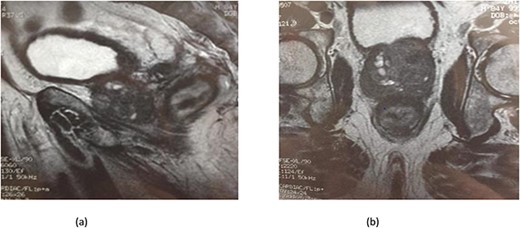

Serum carcinoembryonic antigen was 4.3 μg/L (normal value <5.1 μg/L). Biological tests showed normal platelet count and prothrombin time was 70%. Hemoglobin level was 12.2 g/dL. His biochemical tests showed hypoalbuminemia (31 g/dl). The patient was scheduled for a colonoscopy. However, a large bowel obstruction occurred during the bowel preparation. Thus, computed tomography (CT) scan of the abdomen and the pelvis was performed revealing circumferential wall thickening narrowing the rectal lumen and invading the prostate and the mesorectum with upstream bowel dilatation without extrinsic mass, lymphadenopathy, or metastasis. The patient underwent colostomy without incident. Colonoscopy was performed after colostomy, showing large, circumferential, infiltrative, friable, and stenosing submucosal mass with erythematous overlying rectal epithelium, taking on the appearance of grape clusters (shown in Fig. 1). Mucosal biopsies showed invasive poorly differentiated carcinoma referring at first a neuroendocrine tumor. Second mucosal biopsies were performed showing inflammatory modifications of the rectal mucosa without any malignancy. Third mucosal biopsies concluded to poorly differentiated carcinoma. Magnetic resonance imaging (MRI) of the pelvis showed circumferential wall thickening narrowing the rectal lumen and invading posterior peripheral area of the prostate, the bladder, the left seminal vesicle, and the mesorectum (shown in Fig. 2). The radiologist suggest a rectal cancer (RC) invading the urogenital tract or a PC invading the rectum subject to non-injected MRI. In fact, the MRI was interrupted before gadolinium injection because the patient was claustrophobic. Serum prostate specific antigen (PSA) was then ordered and it was raised at 25.59 μg/L (normal value<4 μg/L). Therefore, macro-biopsies of the rectal mucosa using snare loop were performed showing a poorly differentiated infiltrative carcinoma and immunohistochemical (IHC) stains were strongly positive for PSA and pancytokeratin and negative for anti-CD56 (shown in Fig. 3). Then, a clear diagnosis of PC invading the rectum was established. Bone scintigraphy was performed and was normal. The patient was referred to urology department. He underwent surgical castration. Then, androgen depletion therapy (ADT) was started. A total of 3 months later, there was a good response with his PSA level dropping to 0.5 μg/L. About 3 years after, patient is still alive, but PSA level has increased to 52 μg/L. The CT scan of the thorax, the abdomen, and the pelvis showed a prostatic hypertrophy with loss of the security edging with the rectum without any metastatic involvement.

(a) MRI features: circumferential wall thickening narrowing the rectal lumen and invading the prostate and the mesorectum without extrinsic mass on sagittal section of the pelvis. (b) MRI features: a cross section of the pelvis showing circumferential wall thickening narrowing the rectal lumen and invading the prostate and the mesorectum.